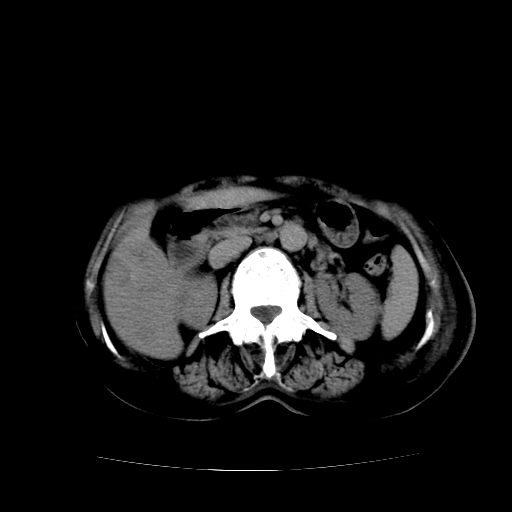

标题: CT17152:女70Y乳腺CA

女70y乳腺ca(针吸活检)

多部位转移瘤的诊断可以肯定,我的疑问是:双肺对称高密度影及胸水是否为心衰肺水肿,病人体虚弱,不好意思图象传的乱![em9]

肺部病变为淋巴转移,肝脏转移,及局部淋巴转移。胸水可能为淋巴回流受阻(血性的考虑胸膜转移)

癌性淋巴管炎,肝脏转移,瓷胆囊

1)左侧乳腺癌并左侧腋窝及纵隔淋巴结转移,两肺淋巴道转移(癌性淋巴管炎),肝脏多发性转移。2)双侧胸腔积液。3)慢性胆囊炎。

5、肝转移瘤;

6、瓷胆囊。